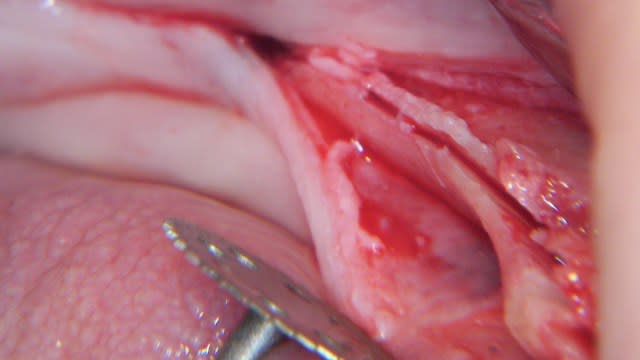

Un exemple de splitting sectoriel au maxillaire sup avec :

- piezo,

- osteotome,

- implant Astra osseospeed,

- comblement par mélange os autogène et BioOss,

- recouvrement par membrane BioGide + conjonctif palatin.

La suite dans quelques mois. ;-))